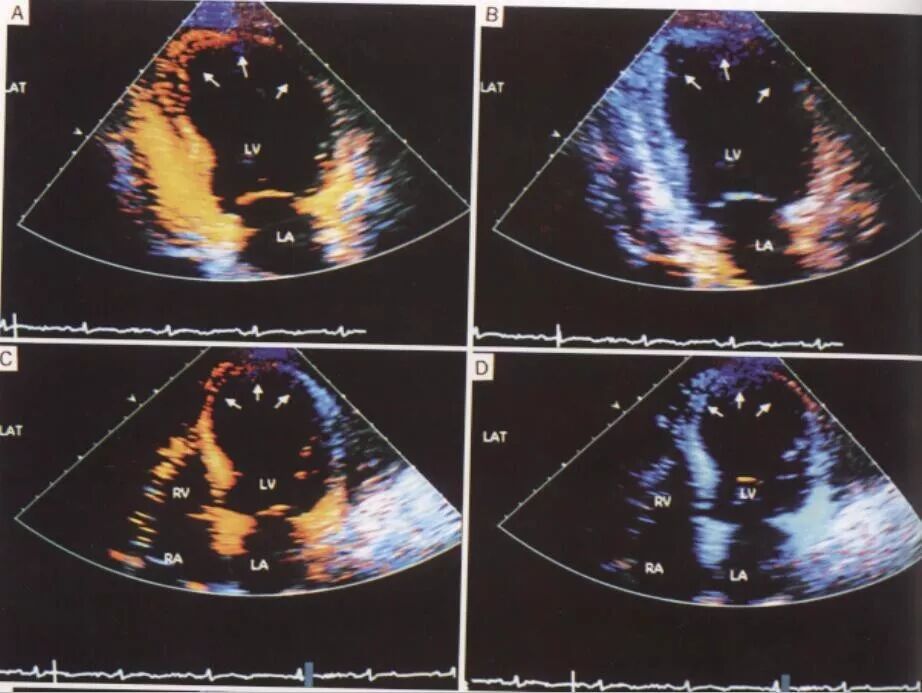

二维超声心动图

可较完整观测左室各壁运动情况。心肌缺血时表现为节段室壁运动异常,主要表现为运动减弱、运动欠协调、运动不同步、室壁扭转。当缺血范围较小时,心室整体收缩功能可在正常范围,心脏大小可为正常;缺血范围较大时,心室整体收缩功能常降低,心腔常增大。